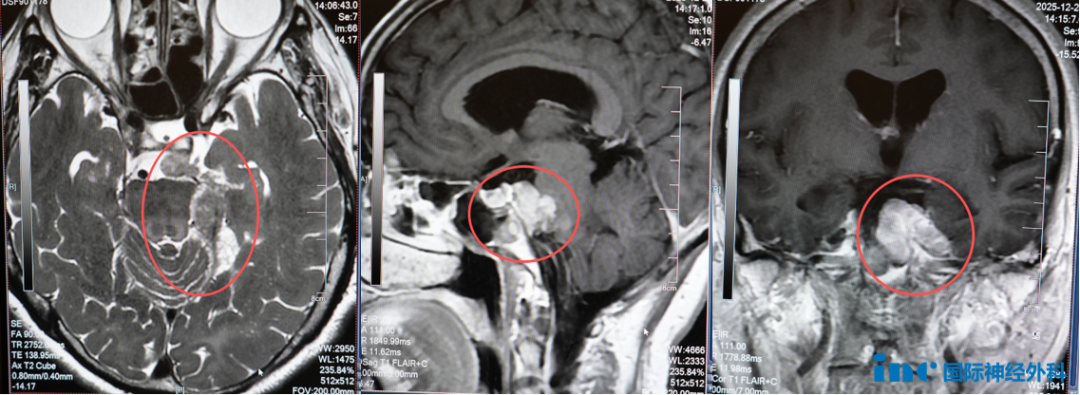

患者为61岁女性鲁女士,脑膜瘤病史长达23年。2003年接受首次开颅手术后,因肿瘤残留症状接受伽马刀治疗;2012年肿瘤复发,行第二次伽马刀治疗。2018年以来,患者出现左侧耳鸣、左侧面部持续性麻木疼痛及面瘫等症状。

巴特朗菲教授术前评估指出,伽马刀治疗后形成的组织粘连显著增加手术难度。肿瘤呈多灶性分布:幕下病灶、颞叶生长病灶及脑干压迫病灶,同时累及三叉神经走行区,此为症状产生的病理基础。

此类手术操作难度极高,正常解剖结构辨识困难,既往开颅手术改变局部解剖关系,术区瘢痕和组织粘连使肿瘤边界分辨极具挑战。巴特朗菲教授凭借40年复杂区域手术经验,采用显微技术精细分离,实现肿瘤最大程度切除,同时有效保护神经功能,手术顺利完成。